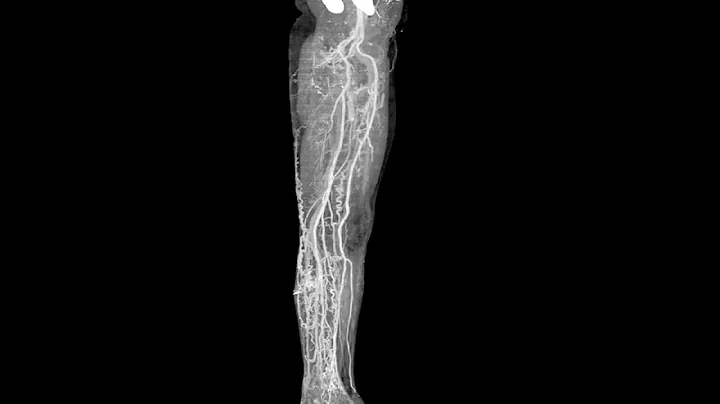

Venograms As A Useful Tool

While at the Northeast Association of Equine Practioners Symposium, Dr. Ric Redden shares his thoughts on the basics of ...